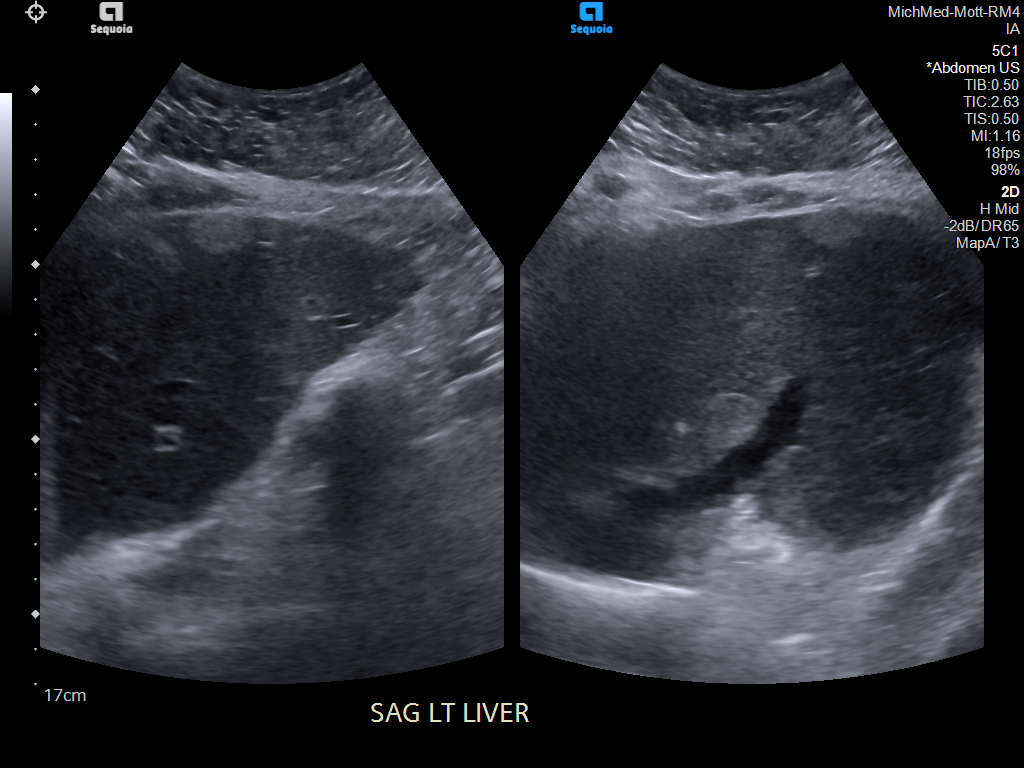

69 M with PMH of HCV cirrhosis & HCC s/p resection in 14 years ago presenting today for a screening ultrasound.

135/73 mmHg / 78 bpm / 16 breaths/min / 96.4°F

sclerae anicteric, no jaundice

CMP wnl, AFP 5